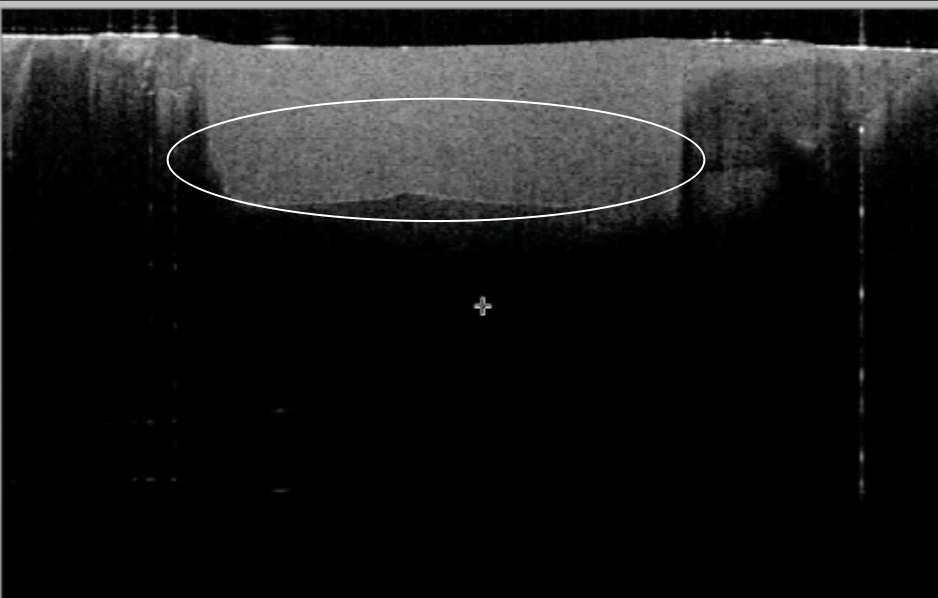

These images from a video in the study Hayashi J, et al. Real-Time Imaging of Gap Progress during and after Composite Polymerization. J Dent Res. 2017; 1-7 show adhesive failure. The first image shows composite placed in a restoration. The second shows the composite after it has been cured, the white line at the bottom showing a gap between the adhesive material and the tooth, which can cause the restoration to fall out or create sensitivity.

We use specific techniques that create a bond to your tooth without this gap, so the bond lasts longer and eliminates sensitivity.